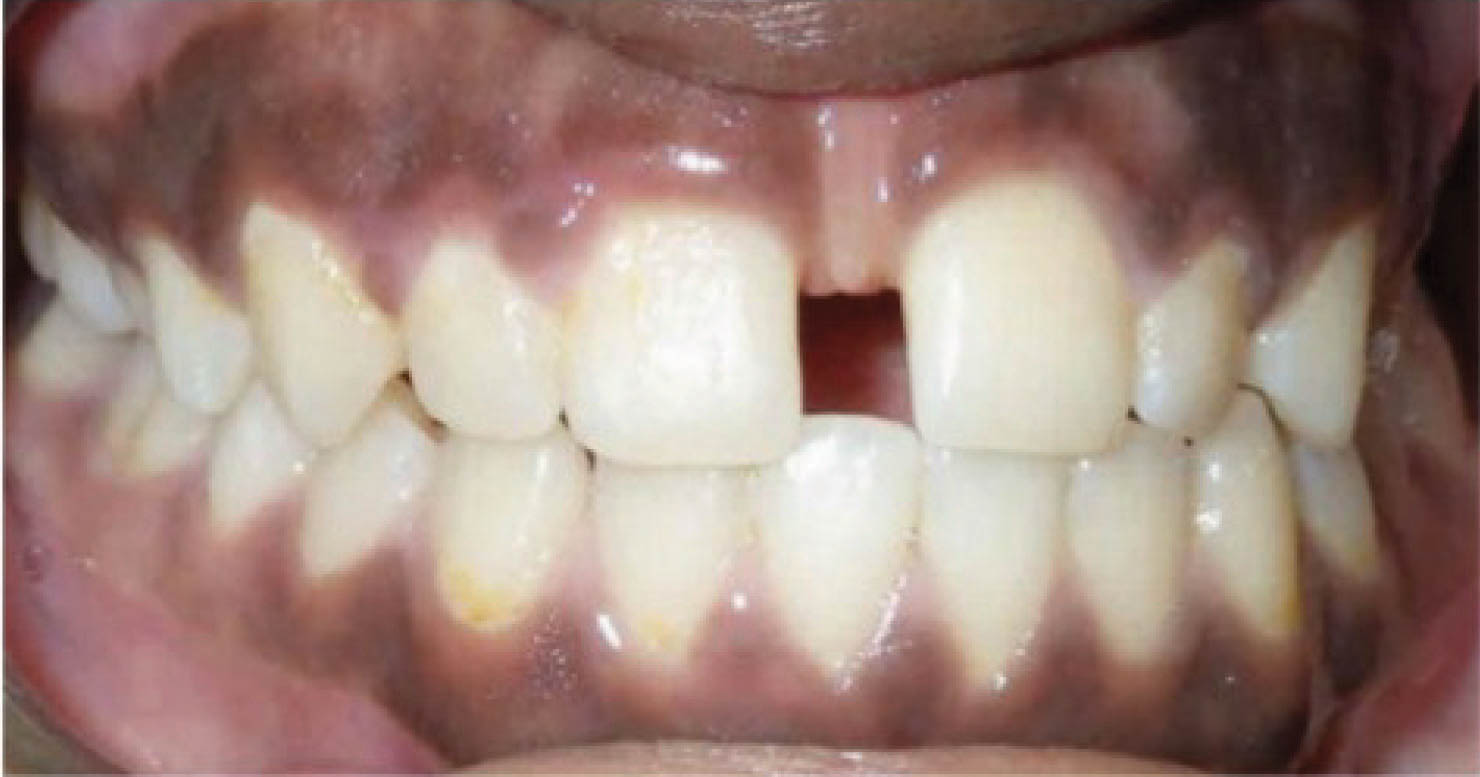

در بیماری که در شکل 38-6 مشاهده میکنید، یعنی بیماری که سانترالهای بالا او از هم به صورت تیپینگ دور شدهاند، درمان با الاینر خیلی عالی میشود، و تصویر آخر نرم افزار به نتیجه درمان خیلی شبیه میشود (شکل 39-6 و 40-6).

شکل 38-6